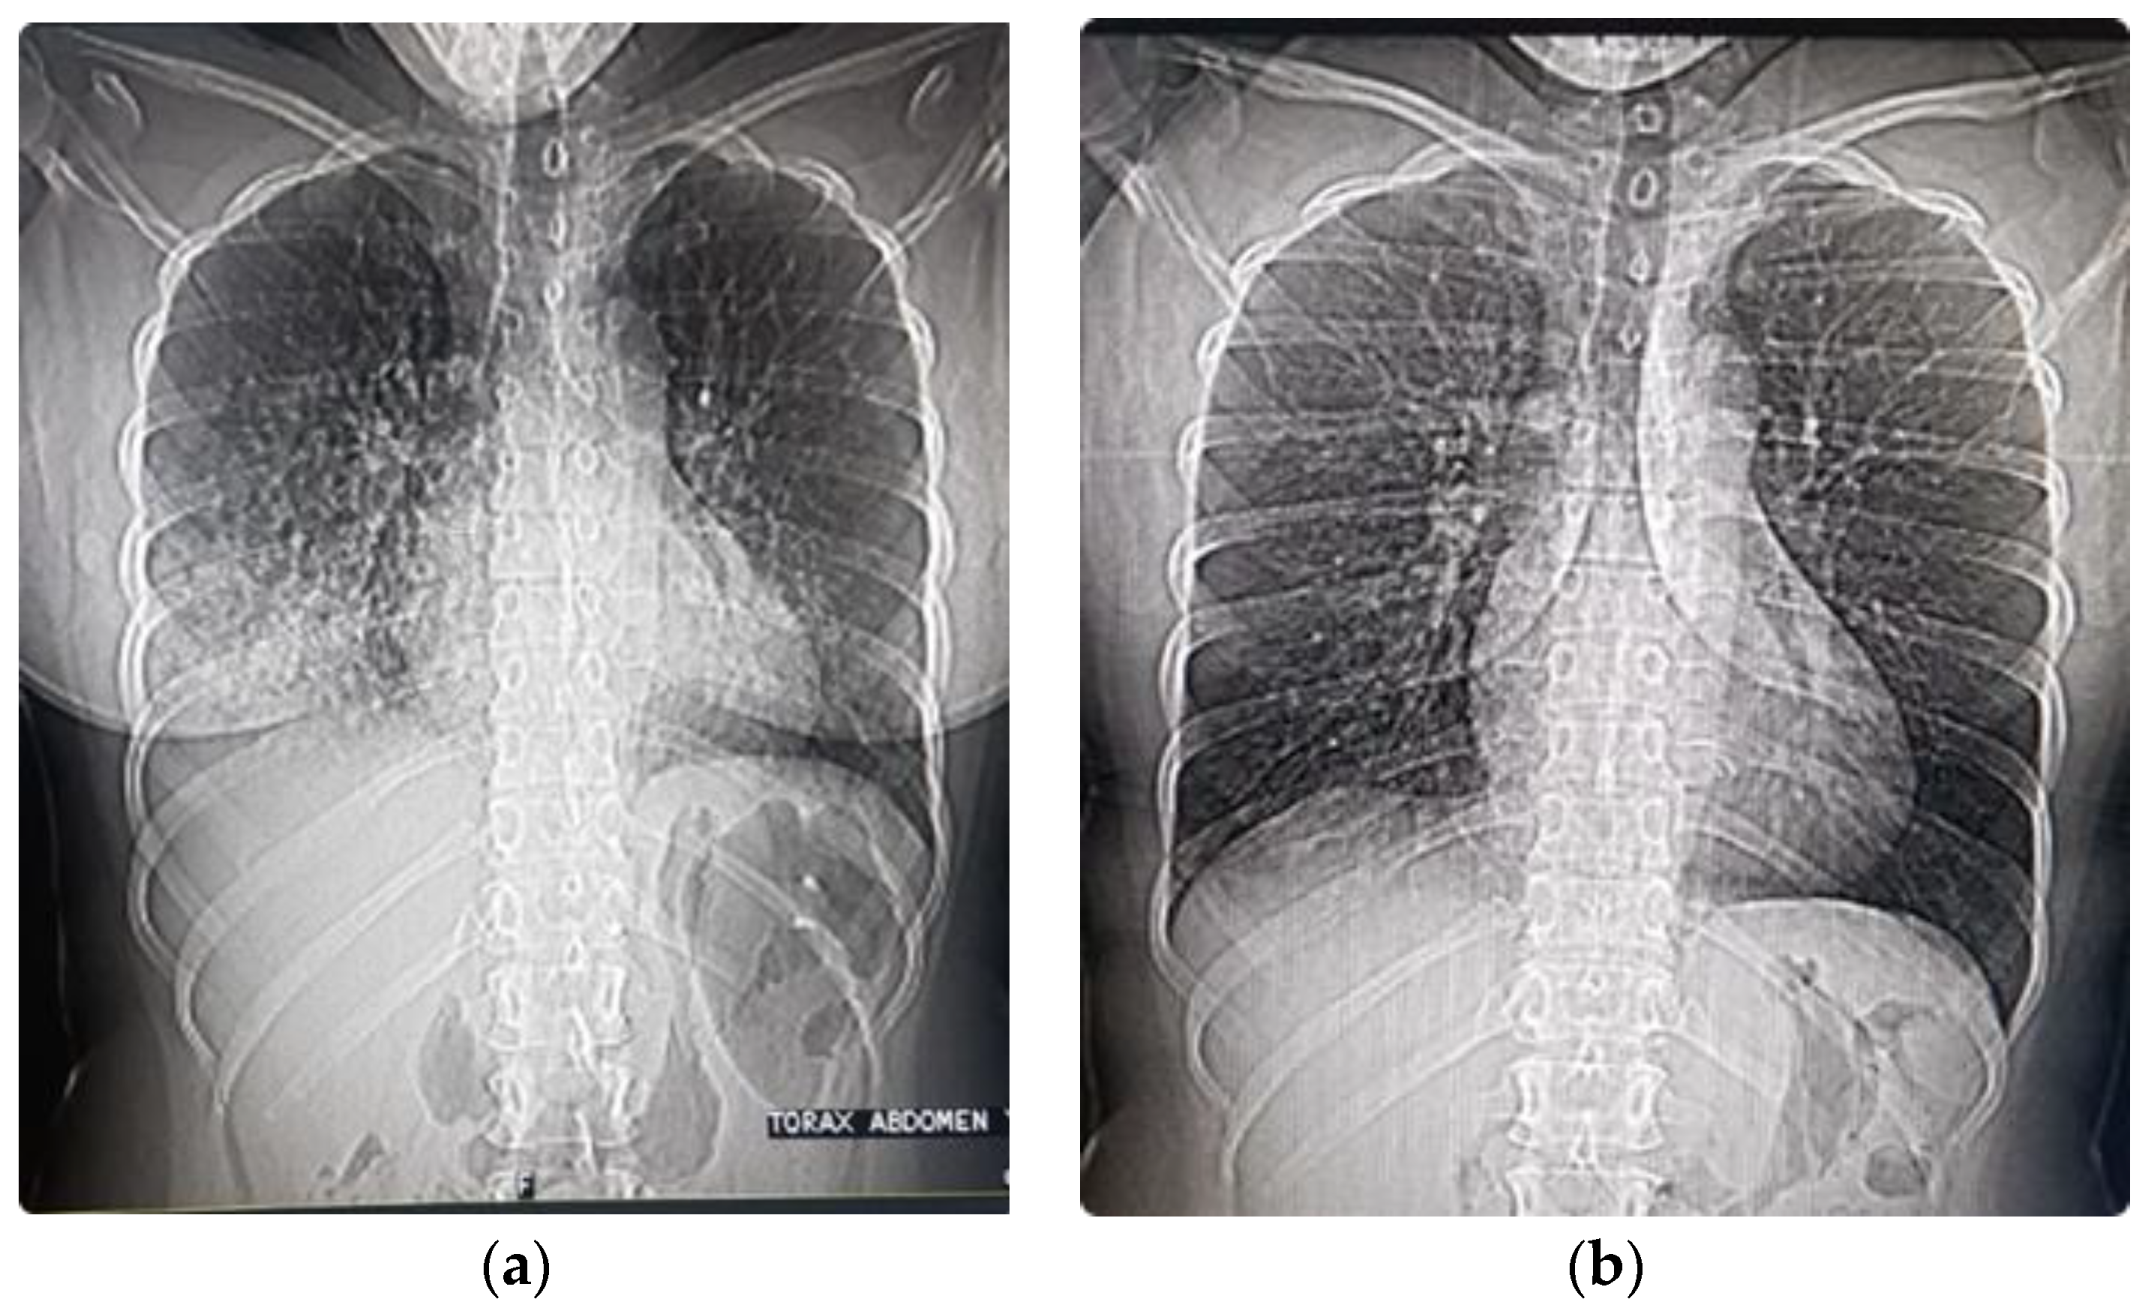

12. AMS Evolving to HAPE and/or HACE

13. Treatment of HAPE and HACE at High Altitude